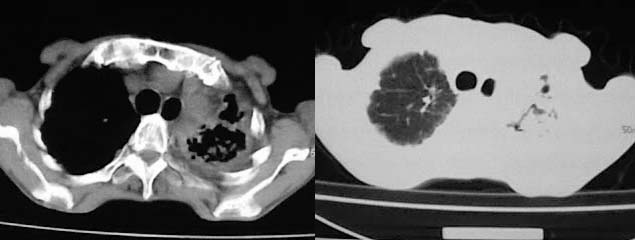

以下是引用有风的日子在2008-5-2 12:13:00的发言:[br][emb10][br][br]肺ca?有病理支持吗?[br][br]我看更象是肺tb并支扩、间质性肺炎。最好拿个病理结果来,不然这点影像资料诊断肺ca是难以服人的![br][br]至于主动脉瘤的诊断问题,国外认为≥4.0cm就可诊断了,国内对此诊断标准更为严格。患者升主动脉明显增粗,即>4cm。你诊断个升主动脉扩张并不为过!

以下是引用zjzjr在2008-5-2 14:39:00的发言:[br]支持双侧继发型肺结核,左侧胸膜肥厚,慢性支气管炎伴间质纤维化.